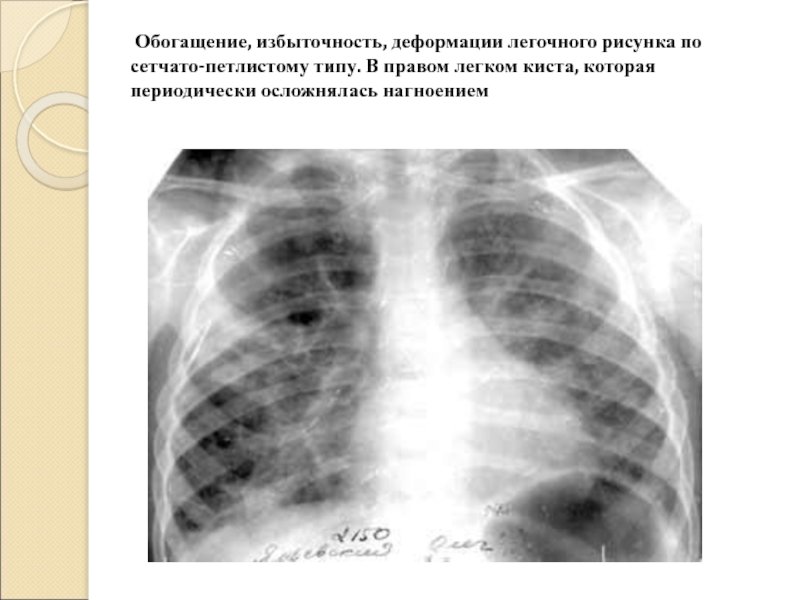

Деформация легочного рисунка